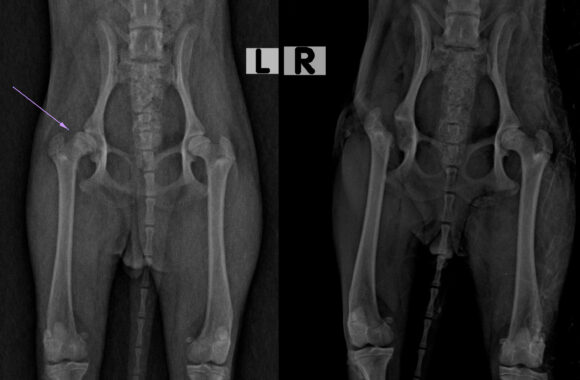

I principali campi d’interesse sono la chirurgia generale e specialistica, l’ortopedia preventiva ed articolare, la traumatologia e la diagnostica per immagini avanzata.

Disponiamo di nuovi locali con avanzate tecnologie ed attrezzature come la TAC VETERINARIA e la RISONANZA MAGNETICA per la diagnostica per Immagini.

Il Servizio Tac Veterinaria a Portici

Attualmente l’unica clinica veterinaria di Napoli e provincia che ha a disposizione una TAC Multistrato da 128 strati in struttura, ultra veloce (total body in meno di 15 sec.), con refertazione in 24h/48h.